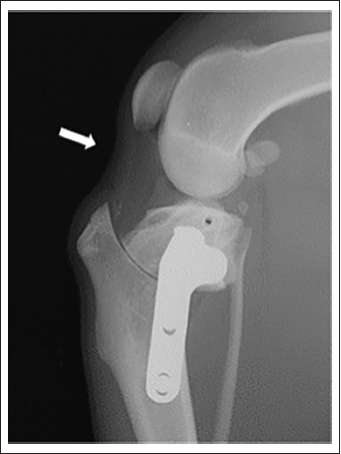

Fig. 1. Mediolateral stifle radiography. Preoperative (A) and postoperative (B) radiographs of TPLO in the same stifle joint and preoperative (C) and postoperative (D) radiographs of CCWO in the same stifle joint.

In each dog, CCWO was performed on one side, as described by a previous report by Christ et al. (2018), while TPLO was performed on the opposite side, as described by Slocum and Slocum (1993). A medial approach was applied. After the arthrotomy, intra-articular structures, including the cruciate ligament and meniscus, were confirmed grossly to be expected, and the joint capsule was sutured. After jig placement, osteotomy was performed based on the preoperative plan. Subsequently, fixation was done using a 2.4-mm diameter TPLO plate (Johnson & Johnson, NJ, USA) in each procedure (Fig. 1). Finally, postoperative radiographs in the mediolateral and the craniocaudal view were obtained as previously described.

Fig. 4. Deflection of the patellar ligament. Mediolateral radiograph of the stifle joint after TPLO. The patellar ligament is caudally deflected (white arrow). TPLO.